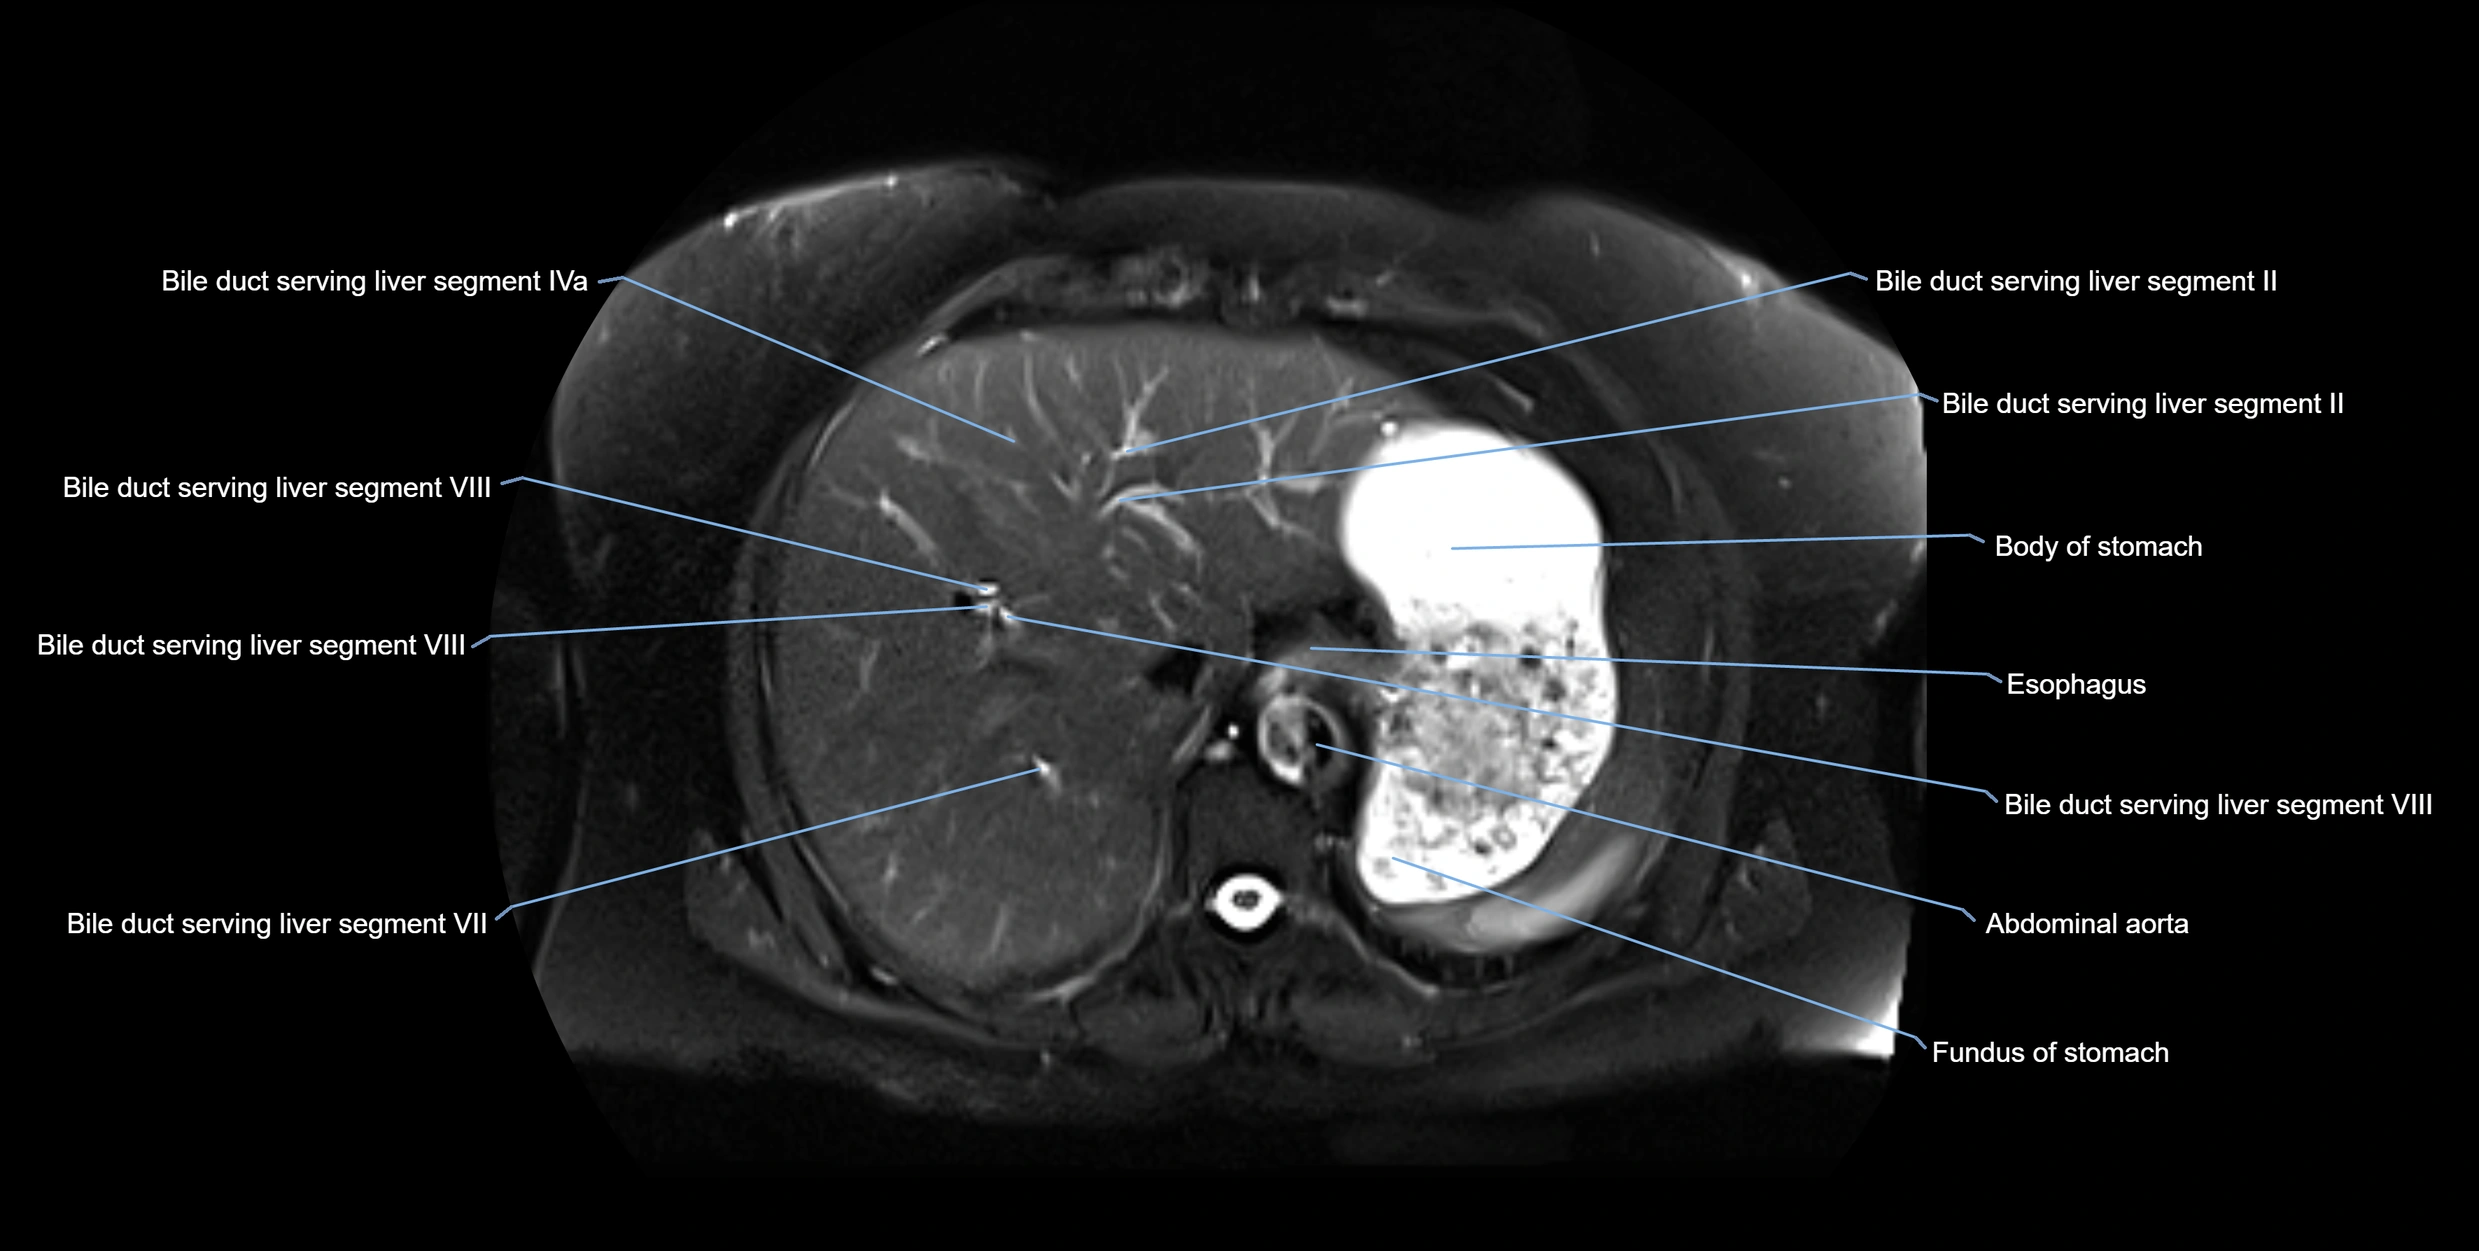

MRI Appearance

T1-weighted images:

• Not typically visualized unless dilated; appears as low signal tubular structure if seen

• Surrounding pancreatic parenchyma shows intermediate signal

T2-weighted images:

• Duct fluid appears bright

• Accessory duct seen as a fine high-signal tubular structure in pancreatic head